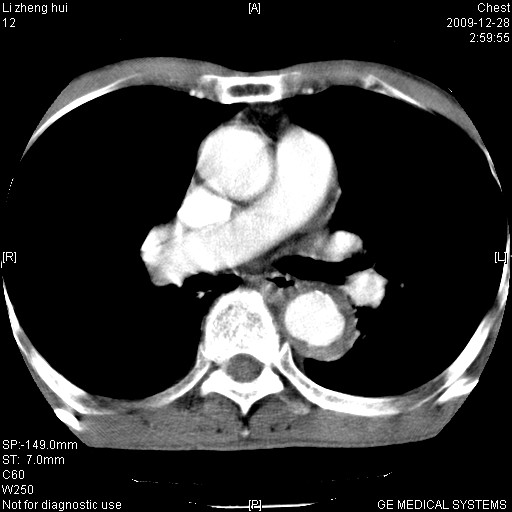

标题: CT23859:胸主动脉瘤

男  79岁 胸部痛急诊入院,晚上做的增强

考虑主动脉瘤?(增粗、钙化、壁血栓?)

支持降主动脉瘤,不考虑夹层

动脉瘤伴附壁血栓

1)考虑胸主动脉壁间血肿或夹层动脉瘤。2)多发性肝囊肿。

1)考虑胸主动脉附壁血栓或夹层动脉瘤。2)多发性肝囊肿。

考虑大动脉炎,附壁血栓形成。